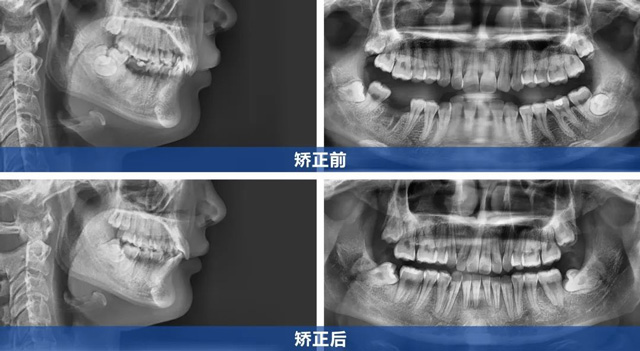

顾客上前牙内扣且咬合较深,属于内倾性深覆合(即上牙覆盖下牙的范围较大,且上前牙向内倾斜,几乎完全覆盖住下牙)。矫正内倾牙时需精准控制前牙外移角度,既要解除深覆合,又要避免上唇过度前凸影响面型。

同时,顾客就诊前缺右下第一磨牙,左下第一磨牙严重龋坏需要拔除,下颌两个磨牙空缺跨度较大,关闭间隙过程中需控制下后牙移动的角度,避免出现邻牙倾斜。

在与顾客充分沟通后,根据顾客诉求及CBCT检查结果,我们制定了拔牙矫治的方案:

1、上颌对称性拔除两颗第一前磨牙,为前牙调整创造空间

2、拔除左下龋坏严重的第一磨牙

3、采用金属托槽精细调整牙齿移动轨迹,排齐牙齿,解除内倾性深覆合

4、利用下后牙向前移动来关闭间隙

5、收完间隙后再整体进行精细调整

杨女士成功告别牙套后,曾经内扣的上前牙变得平直,面部轮廓更显自然流畅,如今的她,笑容自信绽放,举手投足间尽显开朗。